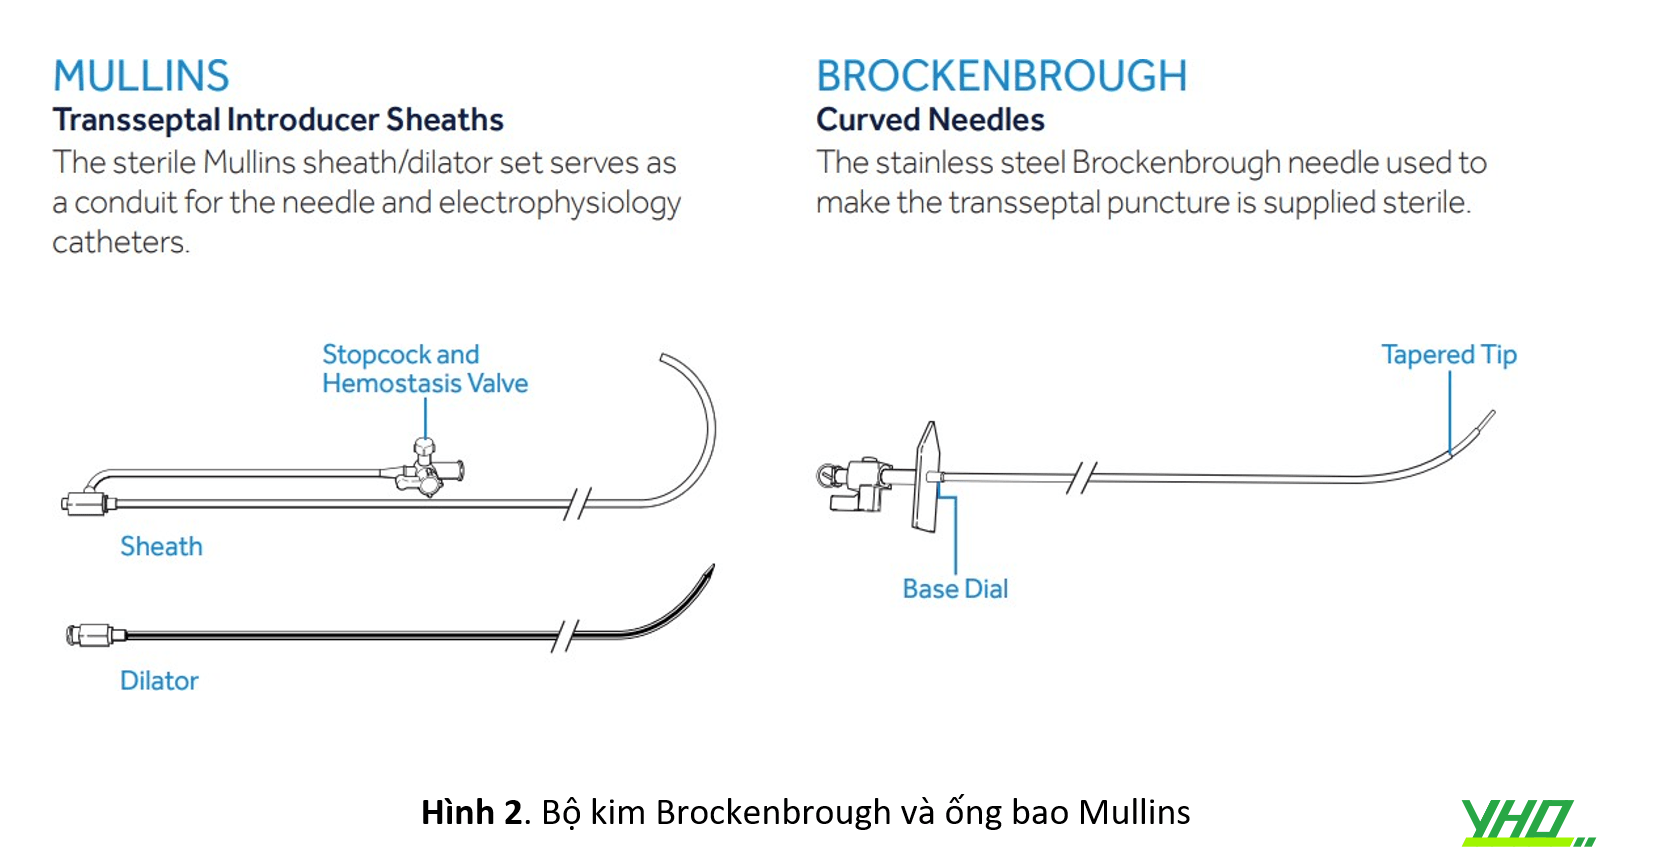

Các loại ống bao (sheath) gốc cong cố định thường được sử dụng: ống bao Mullins (Hình 2), ống thông Swartz (Hình 3).